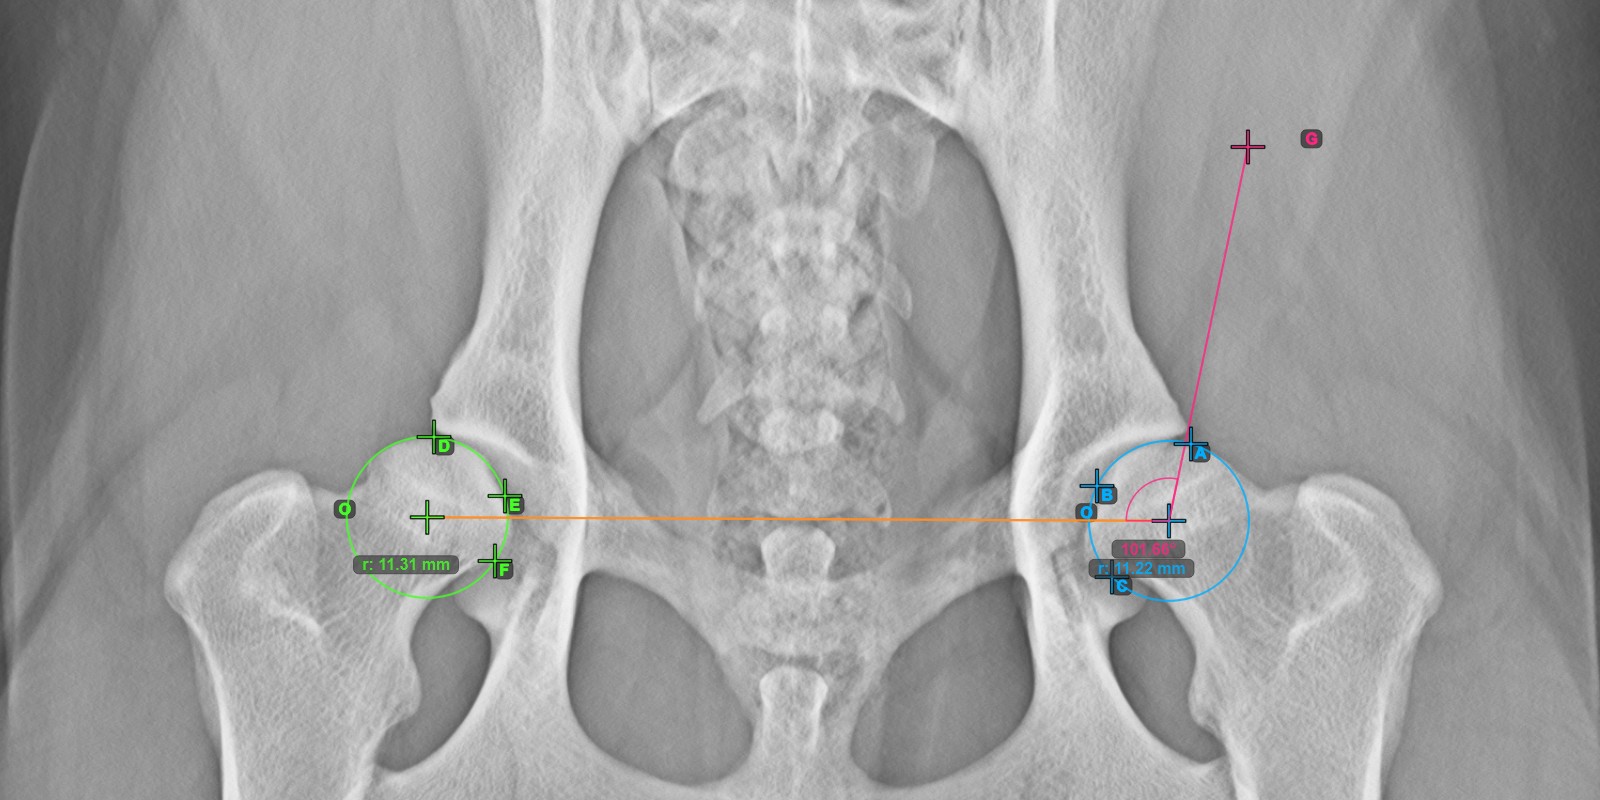

A lenti kép a vonal tipikus elhelyezkedését és a kiszámított Norberg szög mérését ábrázolja.

../../_images/image71.jpg